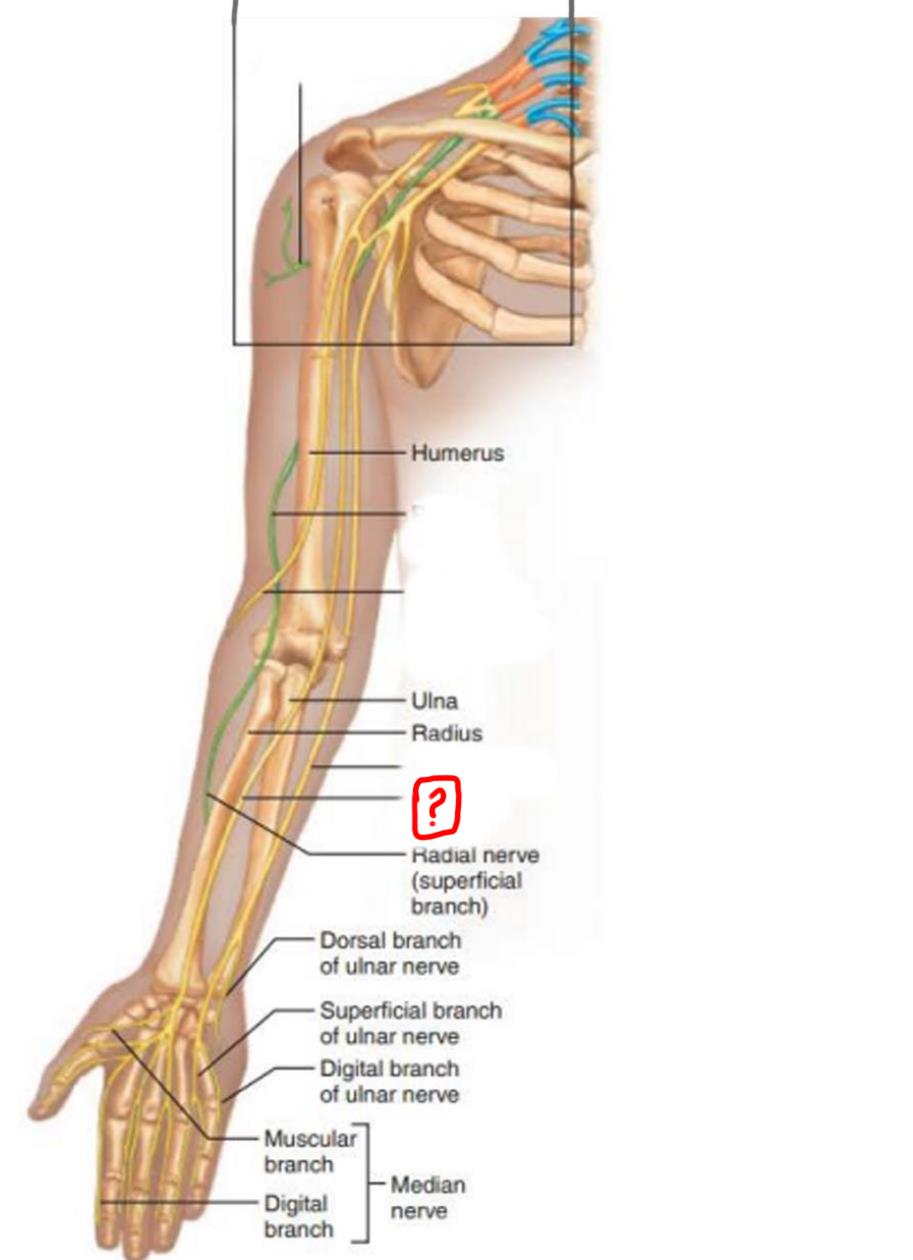

axillary nerve

radial nerve

musculocutaneous nerve

ulnar nerve

median nerve